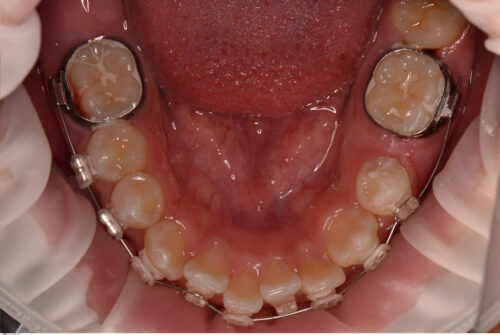

全顎的な歯列矯正も兼ねて治療を開始します。

まずはオープンコイルで萌出するためのスペースを拡大していきます。